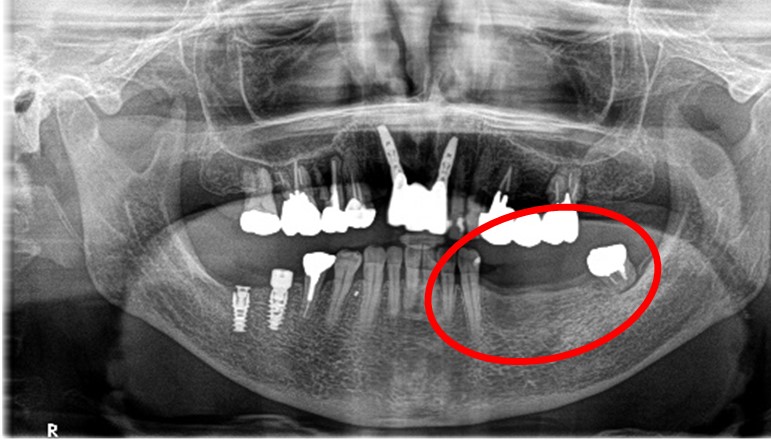

所感

2022年5月に上前歯に2本、2023年12月に右下に2本、インプラント治療をしていましたので、今回も左下3本欠損のところに義歯ではなくインプラントを選択されました。今回も X-Guideを使った埋入で、安心安全に行うことできました。

インプラント2本:¥363,000×2本=¥726,000(税込)

ポンティック1本:¥115,500(税込)

合計:¥841,500(税込)

Before